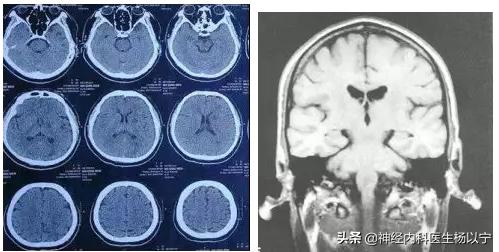

自诉:2月底开始吃中药,已经吃了3个多月,针灸也做过,到现在还是眼睑闭合不全,眼睛一大一小;抬头纹有点斜,鼓嘴漏气,吃饭的时候流眼泪。当时外出时着凉了,次日晨起出现面瘫症状,吃过西药,打过垫底,做过CT检查,遗留下了后遗症没有治好。

诊断:左侧周围性面瘫后遗症(风寒型)